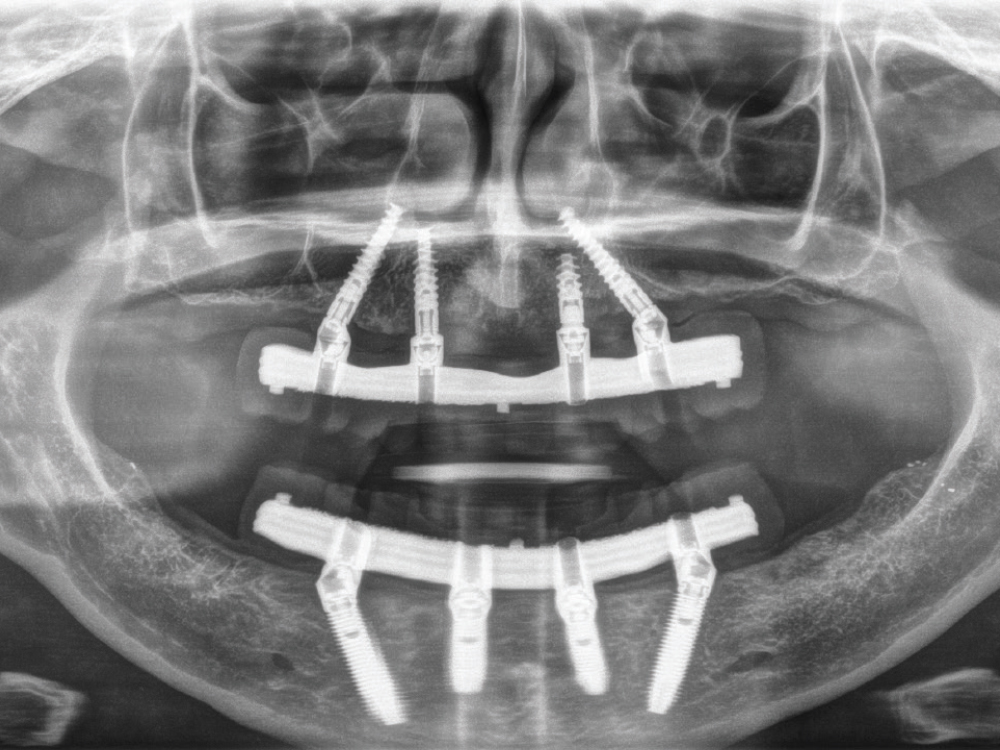

This panoramic X-ray shows traditional maxillary and mandibular All-on-4® hybrid prostheses with milled titanium bars supporting a screw-retained hybrid denture.